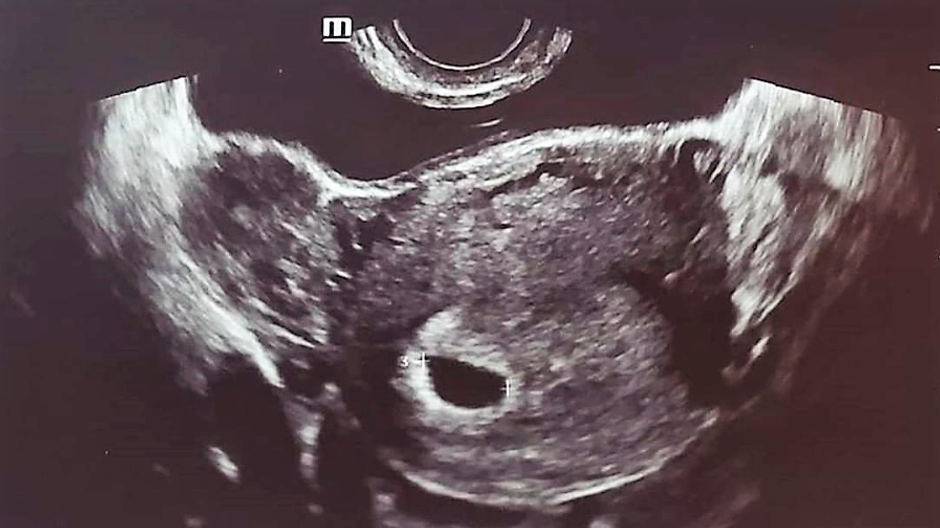

Po správe o mega rýchlom zasnúbení 33-ročnej Amandy Bynes s  Paulom Michaelom, ktorého stretla na protialkoholickom liečení, herečka teraz šokuje ultrazvukovou snímkou na jej sociálnej sieti.

Fotka ultrazvuku zo sociálnej siete za okamih zmizla:

​Správy o rozchode vystriedala úplne iná fotka s komentárom: „Bábätko vo výrobe“. Obrázky boli za krátku chvíľu vymazané z oboch profilov a fanúšikov by iste neprekvapilo, keby išlo o ďalší z jej spôsobov ako získať pozornosť. No tentokrát očitý svedok potvrdil, že Amanda navštívila ambulanciu v Los Angeles a bola celkom rozrušená. Navyše, na obrázku z ultrazvukového vyšetrenia naozaj svietilo herečkino meno.